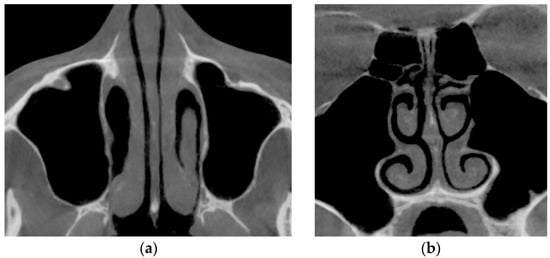

Verification of rhinomanometric data should be performed on the basis of tomographic data of the conditional norm and pathological conditions, which, due to various factors, affect nasal aerodynamics in different ways. Thus, in Figure 12 it is possible to see the characteristic tomographic sections of the nasal cavity at the conditional norm in the axial (Figure 12a) and frontal (Figure 12b) planes.

From Figure 18, it can be seen that at the conditional norm (curve 1), the coefficient of aerodynamic nasal resistance along the length of the nasal cavity increases sharply in the initial area (in the area of the nasal valve), and then there is a relatively smooth growth. When the nasal septum is curved (curves 2 and 3), there is a sharp increase in the coefficient of aerodynamic nasal drag in areas with cross-section numbers 17–25 (total length about 16 mm) and 25–28 (total length about 6 mm), respectively. The contribution of local aerodynamic drag, which is associated with the curvature of the nasal septum depending on the size of the area, is significantly larger in Figure 12 than with a more local offset. In chronic rhinosinusitis (curve 4) with generalized thickening of the mucous membrane of the nasal cavity, the coefficient of aerodynamic nasal resistance is greater than in other cases. During adenoid vegetations (curve 5) in the area (27–31, length about 8 mm), there is a rather sharp (but much smaller than in graphs 2 and 3) increase in the coefficient of aerodynamic nasal resistance, due to the location of aerodynamic resistance in a relatively wide distal part nasal cavity at the exit to the nasopharynx (see Figure 16). After conchotomy (curve 6), the aerodynamic resistance of the nasal cavity is significantly reduced and monotonically increases without abrupt changes and extremes, which is caused by a wide air channel.

The data of the functional study using posterior active rhinomanometry (see Figure 19) in the forced respiration actually fully correspond to the obtained analytical calculations in Figure 18. It can be concluded that the lowest air flow is at the curvature of the nasal septum (curves 2 and 3 on Figure 19), especially when the curvature of the nasal septum is in the middle section (curve 2 in Figure 13), which causes significant overlap of air flow by local resistance and subsequent turbulence of the flow for a considerable length. With generalized narrowing of the nasal canal due to chronic rhinosinusitis (curve 4 and Figure 14) there is also a fairly low air flow, but this is achieved due to a greater pressure drop, and as a consequence, the largest of these pathological coefficients of aerodynamic nasal drag with high pressure has a loss in length. Adenoid vegetations (curve 5 and Figure 16), also due to local narrowing in the nasopharynx, contribute to increased aerodynamic nasal resistance, but its increase is significantly (approximately twice) less than in the effects of chronic rhinosinusitis and curvature of the nasal septum.